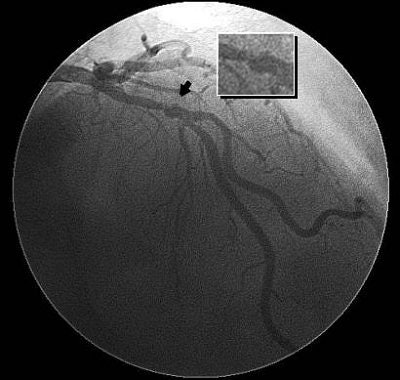

| Coronary CTA images (above) show extraluminal contrast in communication with the coronary lumen, consistent with a ruptured coronary plaque. An invasive angiogram (below) from the same patient showed extraluminal contrast (arrow) representing a ruptured plaque associated with a severe stenosis in the left anterior descending artery. Images courtesy of Dr. John Lesser and Dr. Jamie Pelzel. |